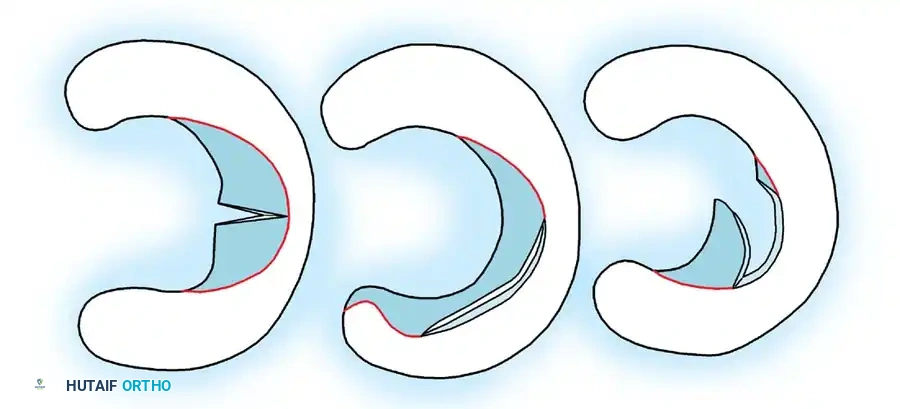

Types of Meniscal Excisions O’Connor separated meniscal excisions into three categories depending on the amount of meniscal tissue to be removed (Fig. 48-15).

C

Fig. 48-15 Types of meniscal excision. A, Partial meniscectomy. B, Subtotal meniscectomy. C, Total meniscectomy. (Redrawn from Shahriaree H: O’Connor’s textbook of arthroscopic surgery, Philadelphia, 1984, Lippincott.)

Partial Meniscectomy In this type of meniscal excision, only the loose, unstable meniscal fragments are excised, such as the displaceable inner edge in bucket-handle tears, the fl aps in fl ap tears, or the fl aps in oblique tears. In partial meniscectomies, a stable and balanced peripheral rim of healthy meniscal tissue is preserved.

Subtotal Meniscectomy In this type of meniscectomy, the type and extent of the tear require excision of a portion of the peripheral rim of the meniscus. This is most commonly required in complex or degenerative tears of the posterior horn of either meniscus. Resection of the involved portion by necessity extends out to and includes the peripheral rim of the meniscus. It is termed subtotal because in most cases most of the anterior horn and a portion of the middle third of the meniscus are not resected.

Total Meniscectomy Total removal of the meniscus is required when it is detached from its peripheral meniscosynovial attachment, and intrameniscal damage and tears are extensive. If the body of the peripherally detached meniscus is salvageable, total meniscectomy is not warranted, and meniscal suture should be considered.